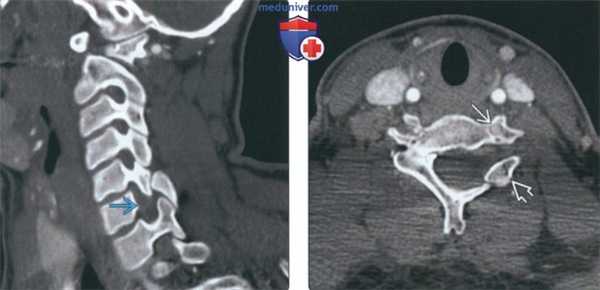

(Слева) На рентгенограмме шейного отдела позвоночника (СКФ II типа) в боковой проекции определяется нарушение сегментации С2-С3 в с наличием рудиментарного межпозвонковою диска и со слиянием остистых отроет-ков С2 и СЗ.

(Справа) На сагиттальной КТ (СКФ II типа) определяется классическое нарушение сегментации С2-С3 с типичным рудиментарным межпозвонковым диском. Также определяется нарушение сегментации остистых отростков С2 и СЗ.

(Слева) На сагиттальной МРТ (Т2 ВИ) визуализируется маленький рудиментарный межпозвонковый диск на уровне С2-С3 (врожденное нарушение сегментации). Также определяется тяжелый стеноз позвоночного канала вследствие гипоплазии дуги С1.

(Справа) На корональной MPT (Т2 ВИ) у ребенка с врожденным нарушением сегментации С2-С3 определяется гипоплазия диспластического зубовидною отростка с наклоном его вправо. Слегка асимметричное поражение рудиментарною диска С2-С3 приводит к легкому сколиозу шейного отдела позвоночника.